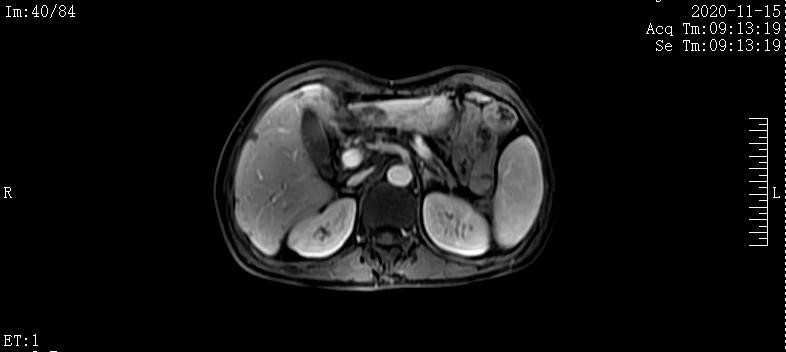

2020-4-20肝脏MRI提示:肝内多发团块,肝门及腹膜后淋巴结肿大;胰腺体尾部团块

2020-6-17肝脏MRI提示:1.胰腺体尾部异常信号,较前略缩小。2.肝内多发结节及团块,考虑转移瘤,部分病灶较前缩小。3.腰1-3椎体异常信号强化范围较前略缩小

2020-8-22肝脏MRI提示:1.肝脏多发异常信号,较前稍缩小。2.腰椎内异常信号,较前缩小

2020-11-15